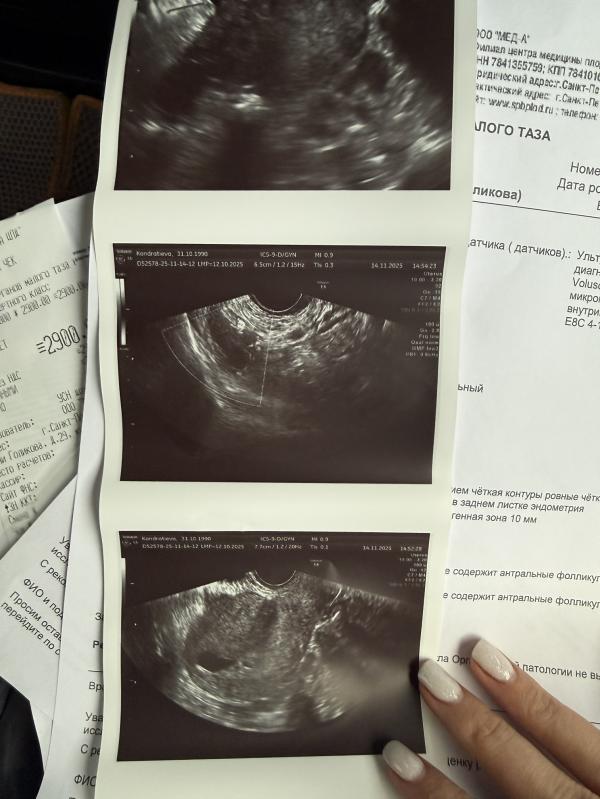

Что скажите , задержка тест //

14.11.2025

Для узи пока просто рано, можете сдавать хгч, а можете просто на узи через 7-10 дней сходить ещё раз)

Может еще рановато пошли

Вам бы хгч сдать

При хгч от 1000 что-то видно

Сколько задержка? Рано пришли на узи))

@kondr31101990, через пару недель только плодное видно, а еще через 2 эмбрион и сердце